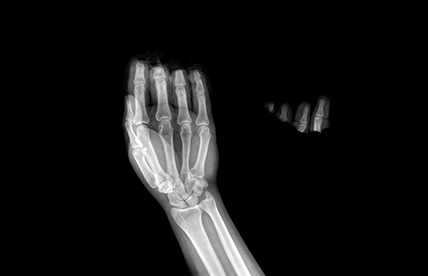

PARMAK VE EL KIRIKLARI

Parmak ve el kemik kırıkları, düşme, çarpma veya iş kazaları sonrası sık görülür. Şişlik, ağrı, morarma ve hareket kısıtlılığı ile kendini gösterir. Bazı kırıklarda parmaklarda şekil bozukluğu gelişebilir. Yer değiştirmemiş kırıklarda atel veya alçı ile tedavi yeterli olabilir. Kaymış veya eklem içine uzanan kırıklarda cerrahi gerekebilir. Parmak kırıkları daha büyük kemik kırıklarına göre bazen daha zorlu olabilir. Cerrahi sırasında büyütücü gözlükler ve hassas aletlere ihtiyaç duyulur. Ameliyatta çok ince teller, mikro-vidalar veya plaklar kullanılarak kemikler sabitlenir. Tedavi sonrası erken dönemde başlanan egzersizler, parmak hareketlerinin ve el fonksiyonunun geri kazanılmasında önemli rol oynar.